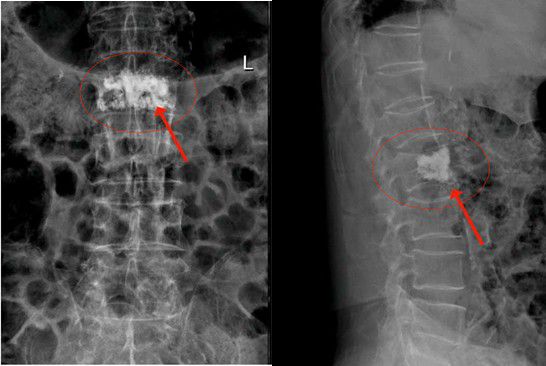

△腰椎第二椎體(L2)壓縮性骨折

2月3日陳大伯由家人送到我院治療,收入外四科(骨科)。經腰椎MR檢查,發現腰椎第二椎體(L2)壓縮性骨折,椎體中間前緣壓縮變空。高齡患者如果采用保守治療,往往骨折遷延難愈,需要卧床至少1個月以上。老年人基礎疾病多,如陳大伯就患有高血壓、糖尿病、陳舊性心肌梗死等疾病,長期卧床容易誘發各類并發症而危急生命。而傳統開放性手術創傷大,高齡患者難以承受。這也是以往老年人最怕骨折的原因。